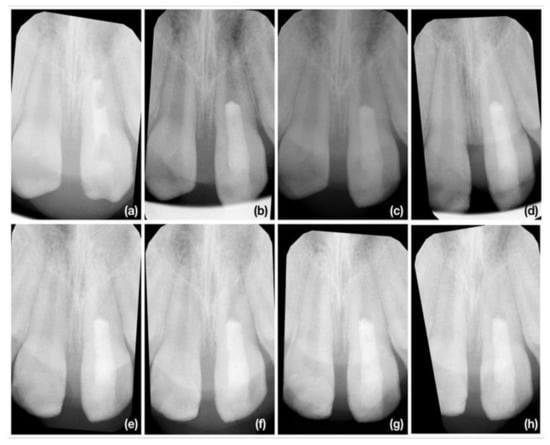

2.4. Radiographic Assesment

2.4.2. Radiographic Root Length Measurement

2.4.3. Radiographic Root Width Measurement

2.4.4. Radiographic Root Area Measurement

3.2. Radiographic Root Length Change

3.3. Radiographic Root Width Change

3.4. Radiographic Root Area Change